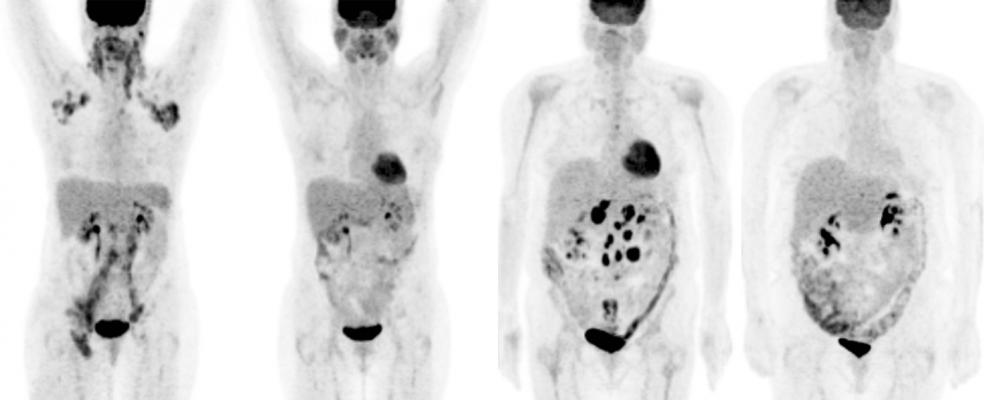

A study supported by blue earth diagnostics showed that physicians can be trained to successfully interpret axumin pet scan images of patients with suspected recurrence of prostate cancer. Axial pet a and fused pet ct b images show a subcentimeter focus of moderately intense facbc uptake arrowhead in the central pelvis. Axumin 18 fluciclovine is a radiopharmaceutical that is proving to be a game changer particularly in the field of prostate cancer detection previously clinicians in the u s. This has some major limitations for prostate imaging such as bladder interference and a reliance on physical changes within the body to.

Axumin uptake may occur with other cancers and benign prostatic hypertrophy in primary prostate cancer. Thereafter the patient was referred to our center for axumin pet scan. Axumin uptake may occur with other cancers and benign prostatic hypertrophy in primary prostate cancer. The bone scan did not reveal any suspicious bony metastasis.